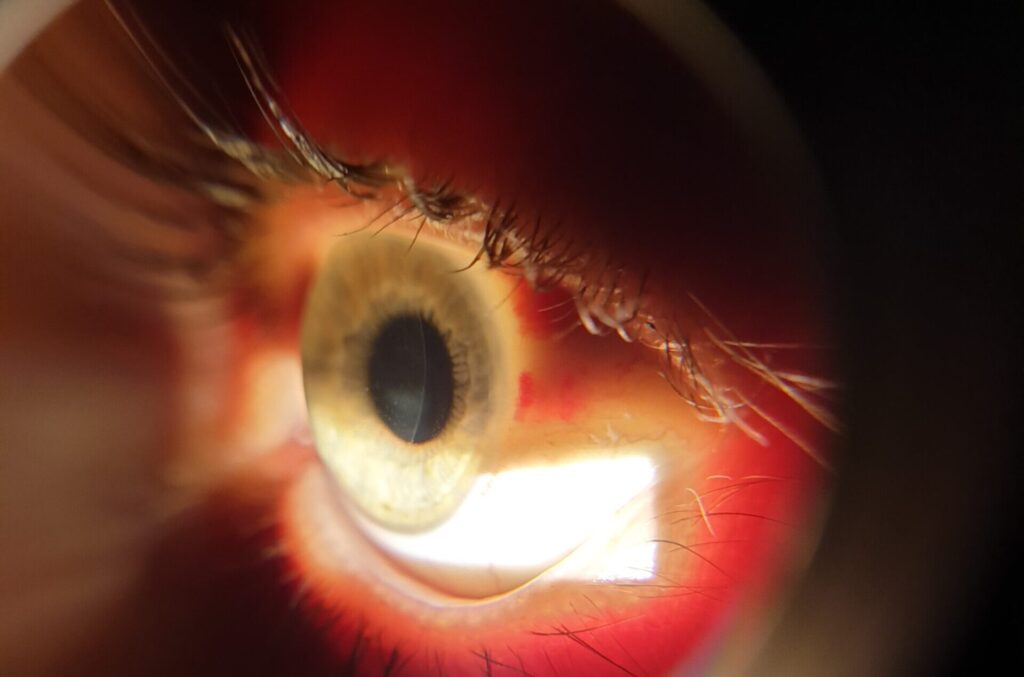

Ο κερατόκωνος είναι μια κατάσταση που επηρεάζει τον κερατοειδή – το διαφανές «παράθυρο» του ματιού μέσω του οποίου περνά το φως. Όταν ο κερατοειδής αρχίζει να λεπταίνει και να χάνει το κανονικό σφαιρικό του σχήμα, αποκτά μια πιο κωνική μορφή, γεγονός που οδηγεί σε θολή ή παραμορφωμένη όραση. Η πάθηση συνήθως ξεκινά στην εφηβεία ή νωρίς στην ενήλικη ζωή και εξελίσσεται σταδιακά, συχνά με διαφορετική βαρύτητα σε κάθε μάτι.

Ο κερατόκωνος ανιχνεύεται με ειδικές εξετάσεις που απεικονίζουν το σχήμα και το πάχος του κερατοειδούς. Η τοπογραφία και άλλες σύγχρονες μέθοδοι δίνουν μια πλήρη εικόνα της κατάστασης, ώστε να επιλεγεί η σωστή αντιμετώπιση.